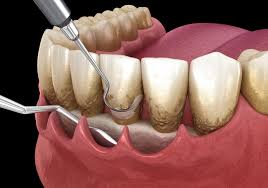

Is Laser Dentistry safe for gum treatment?

Yes. Laser dentistry is extremely safe and minimally invasive. At EndoElite, we use advanced dental lasers for gum surgery, depigmentation, and soft-tissue procedures with faster healing and minimal discomfort.